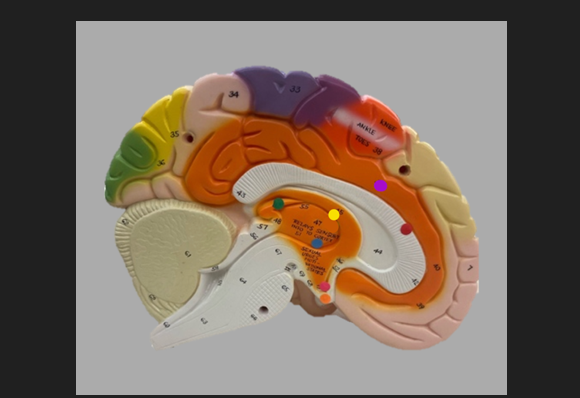

orange dot

frontal lobe

blue dot

longitudinal fissure

dark green dot

precentral gyrus

pink dot

postcentral gyrus

yellow dot

central sulcus

white dot

parietal lobe

light green dot

Broca’s Area

red dot

Wernicke’s Area

orange dot

occipital lobe

blue dot

parieto-occipital sulcus

blue dot

olfactory tract

red dot

corpora quadrigemina

dark green dot

cerebral aqueduct

blue dot

cerebral penduncles

pink dot

pons

orange dot

medulla oblongata

yellow dot

mammillary body

red dot

corpus callosum

dark green dot

pineal gland

yellow dot

epithalamus

blue dot

thalamus

orange dot

optic chiasm

pink dot

infundibulum

purple dot

cingulate gyrus

yellow dot

pituitary gland

dark green dot

pyramids

red dot

olives

blue dot

optic tract

purple dot

midbrain

green dot

folia

orange dot

arbor vitae

yellow dot

fourth ventricle

red dot

vermis

blue dot

hypothalamus

pink dot

cerebral hemispheres

yellow dot

lateral sulcus

red dot

lateral ventricles

blue dot

hippocampal gyrus

green dot

olfactory tract